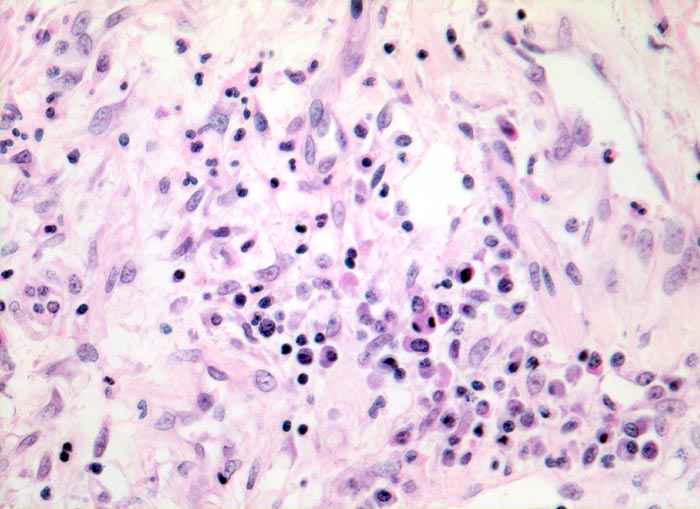

Diffuser Alveolarschaden: proliferative Phase

Stark verbreiterte Alveolarsepten mit Fibroblastenproliferaten, Gefässeinsprossungen und gemischtem Entzündungsinfiltrat aus Lymphozyten, Histiozyten und Granulozyten.

Makroskopischer Lungenbefund: schwere, wässrige und verfestigte dunkelrote Lungen aus denen sich nur wenig Flüssigkeit auspressen lässt.

Hospitalisation wegen akuter nekrotisierender Pankreatitis. Am zweiten Hospitalisationstag entwickelt der Patient ein ARDS (Adult Respiratory Distress Syndrome) mit rasch progredienter Dyspnoe und Tachypnoe, sowie einer Hypoxämie, welche im Verlauf auf Sauerstoffgabe nicht mehr anspricht. Das Thoraxröntgenbild zeigt bilaterale diffuse Verschattungen. Der Patient verstirbt trotz Intensivmassnahmen am 9. Tag nach Spitaleintritt am Multiorganversagen.

Vergrösserung